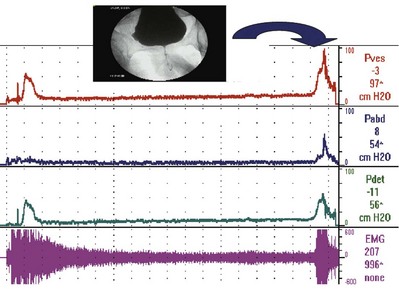

UDS can evaluate the critical parameters during the voiding phase: detrusor contractility, relaxation of the bladder outlet, and coordination of sphincters (Fig. 62–13).

Figure 62–13 Multichannel urodynamics study showing filling and voiding phases with pressure and electromyography (EMG) readings. In this case, the patient experienced an involuntary detrusor contraction (IDC) that led to increased external sphincter contraction and an increase in EMG activity (guarding reflex). However, shortly after that the patient is given permission to void. First there is quieting of the EMG (sphincter relaxation) followed by an increase in Pdet and volitional voiding with a normal-appearing uroflow curve.

Normal voiding requires external sphincter relaxation followed by contraction of the detrusor. The external sphincter (and internal sphincter) should remain relaxed until voiding is complete. In normal voluntary voiding, a rise in detrusor pressure is preceded by a fall in urethral pressure and relaxation of the external sphincter as measured by electromyography (EMG). The sphincter and urethral pressure remain low during voiding and then increase when voiding is completed (Fig. 62–17). Failure of the sphincter to relax or stay completely relaxed during micturition is abnormal (Abrams et al, 2002). Thus normally EMG activity decreases before a voluntary bladder contraction; however, it is not abnormal for EMG activity to increase with an involuntary contraction as part of a guarding reflex to inhibit the IDC (see Fig. 62–11).